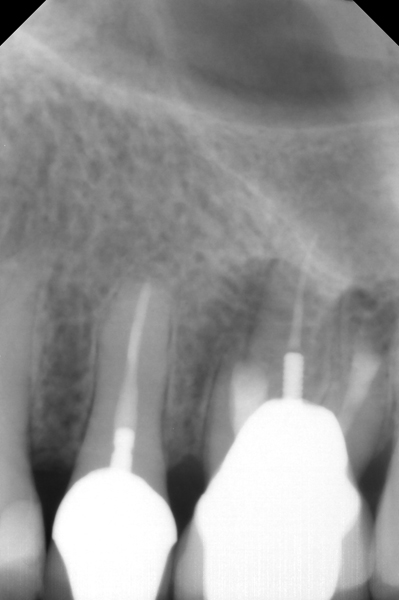

Fig 5. Working length confirmation.

Figure 5

Fig 6. Postoperative radiograph.

Figure 6

Fig 7. 1-year follow-up showing a healthy lamina dura and root development.

Figure 7

Fig 8. 3-year follow-up showing continued root development.

Figure 8